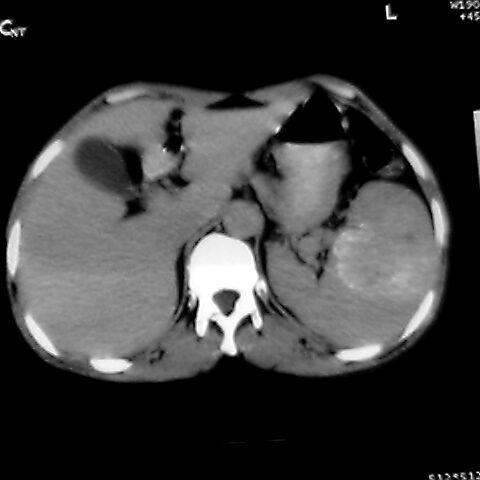

女 48岁 食道癌术前体检发现脾占位。

1肝右下叶小囊肿2右肾上极囊肿或错构瘤3脾脏不典型血管瘤可能性大.

考虑脾脏血管瘤,中央低密度为血栓形成

脾脏低密度灶伴钙化,增强化明显,中心见液化坏死灶,强化延时明显。考虑血管瘤。转移瘤待排。

1,脾血管瘤。2,右肝,右肾小囊肿。